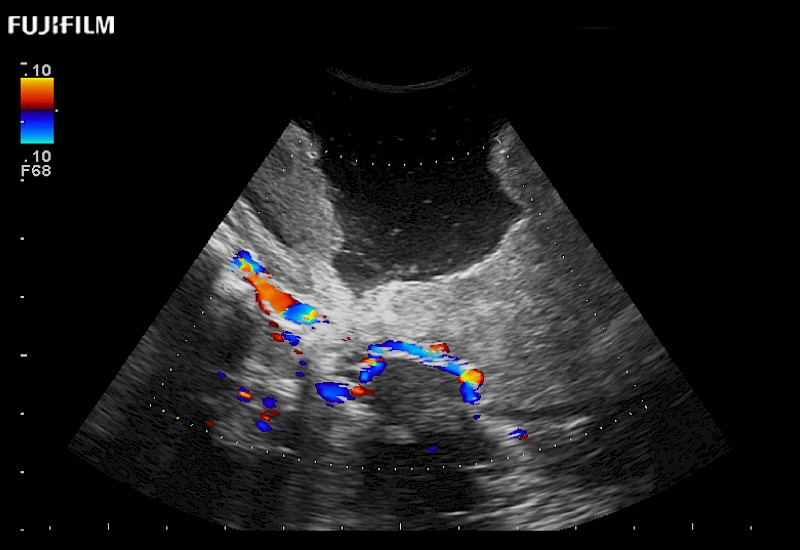

Exclusive 10mm side‐fire linear array transducer with 2.87mm diameter is ideal for real‐time visualization through and behind structures and instant, scalable definition of anatomy and vascularity including the ability to delineate and define tumor margins.